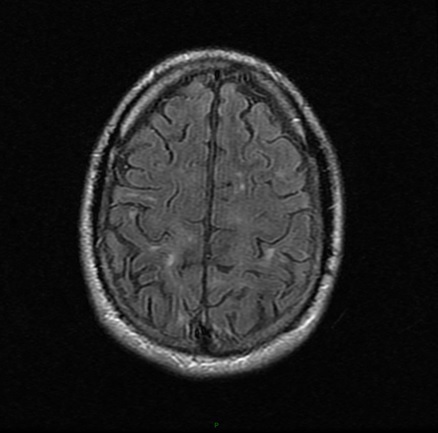

L’auxiliaire de vie vous a rapporté les résultats d’une imagerie par résonance magnétique (IRM) cérébrale réalisée il y a dix jours sur la prescription de son neurologue.

Question 7 : Parmi les propositions suivantes, laquelle (lesquelles) est (sont) exacte(s) ?

Les hypersignaux FLAIR sont dans la substance blanche (principale zone myélinisée du cerveau)

Il n’est pas possible de distinguer l’ancienneté d’une plaque sur les séquences FLAIR (la prise de contraste après injection de gadolinium permettra de confirmer qu’il s’agit d’une plaque active).

Les lésions observées sont donc compatibles avec le diagnostic de sclérose en plaques, mais leur ancienneté est inconnue et leur responsabilité dans les troubles de la vigilance du patient est très improbable.